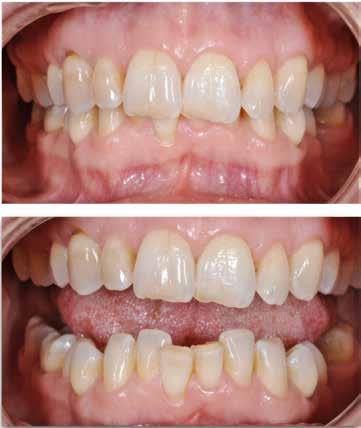

I samråd med patienten og egen tandlæge* afstemmes forventningerne, inden der bestilles refinement alignere. Nivelleringen af alle tænder i tandbuerne, smilelinje og -kurve samt den bukko-lingvale position af incisiverne foretages og efterfølges af retainers lingvalt på over- og underkæbeincisiver (Fig. 3 A-D). Hele behandlingen udføres under løbende kommunikation med patient og egen tandlæge*, der udfører den efterfølgende rekonstruktion med direkte plast (Fig. 4 A-D). Behandlingsvarigheden har været to år og to måneder, hvor ortodontien har forløbet over 21 måneder. Der har været anvendt et første sæt på 66 alignere samt yderligere to sæt med ni refinement alignere. Tandblegning og direkte plastrekonstruktion er udført af egen tandlæge* (Fig. 5 A-F).

Fig. 5. A, B. Smil og kæbeforhold før og efter. Et bredere smil med korrektion af de laterale mørke rum. C-F. Harmonisk hældning af overkæbe- og underkæbeincisiver, rekonstruktion af den tabte tandsubstans efter nivellering af gingivaniveau og optimal bukko-lingval placering til direkte plastbehandling.

5. A, B. Smile and jaw relationships before and after. A wider smile with correction of the lateral dark spaces. C-F. Harmonious inclination of the upper and lower jaw incisors, reconstruction of the lost tooth substance after leveling the gingival level, and optimal bucco-lingual positioning for direct plastic treatment.

RESULTATER – Begge patienter opnåede sunde parodontale forhold, funktionel okklusion og forbedret æstetik. Ortodontisk behandling blev iværksat efter opnåelse af parodontal stabilitet og tilpasset det reducerede parodontium med kontrollerede kraftsystemer. Under behandlingen blev parodontiet vedligeholdt, og efter afsluttet ortodontisk behandling blev patienterne fulgt med regelmæssige kontroller af både parodontal sundhed og ortodontisk retention.

Behandlingen afsluttes med yderligere refinement-alignere for finindstilling af okklusionen, og efter 11 måneders ortodontisk behandling er der opnået normale relationer i alle tre